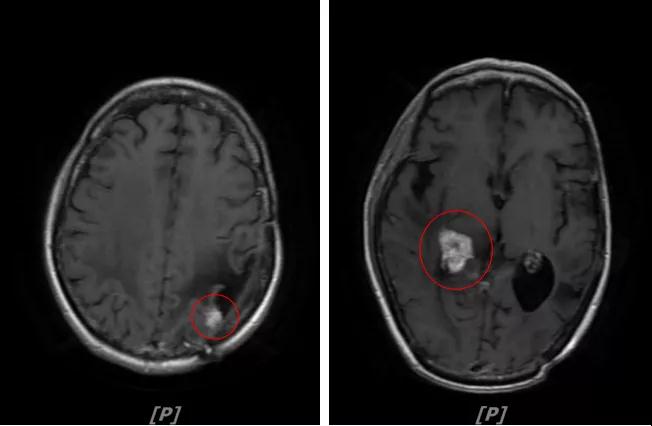

b.2014年3月全脑放疗结束后,予以LX方案治疗(拉帕替尼 1250mg qd+卡培他滨 1500mg bid)。每3个月规律复查,未见明显异常。下图为2014年6月患者行头颅增强MR检查,提示左顶叶脑转移瘤术后改变。

每3个月规律复查,未见明显异常。如2015年8月 头颅MR检查,提示:左顶叶脑转移瘤术后放疗后改变,对比前片2015年3月10日相仿。